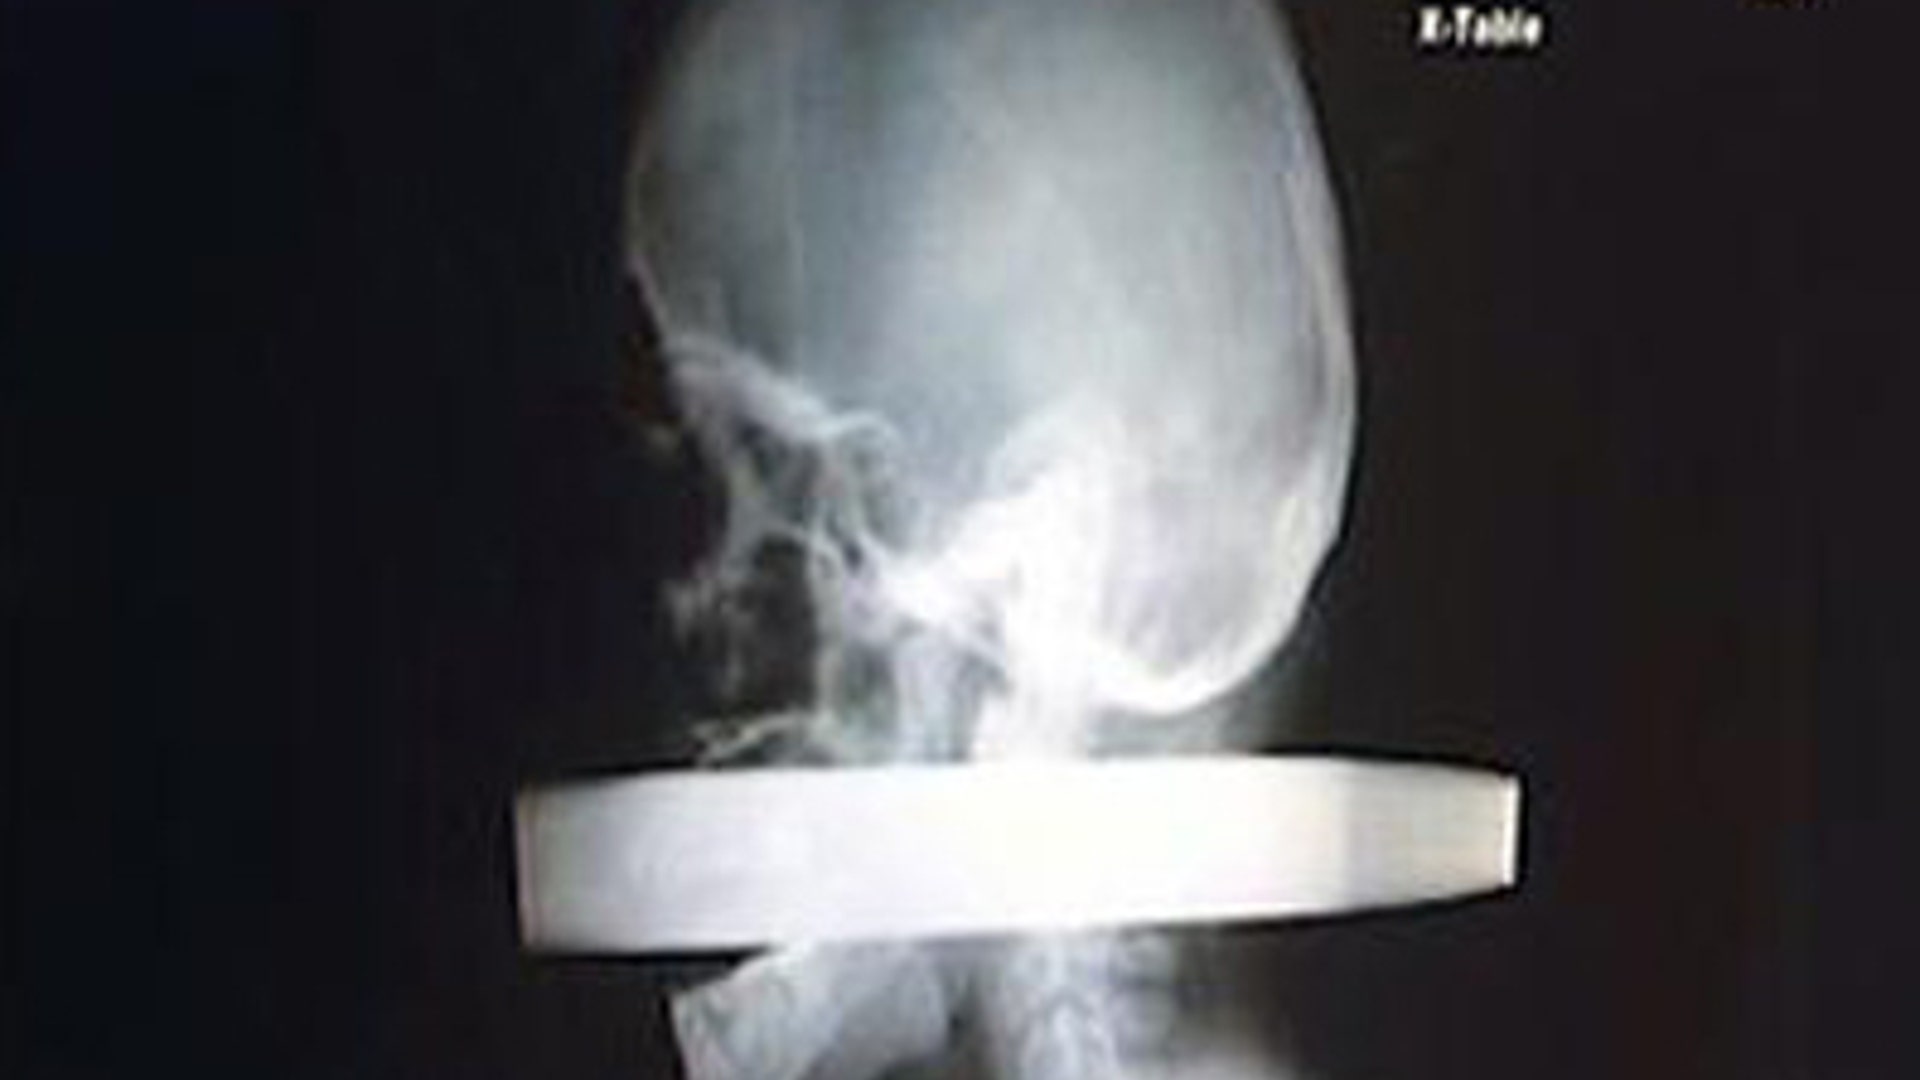

Xiao Wei, 16, who was attacked in a dispute over the video game he was playing, was able to walk into the emergency room entrance of Jillin University with the 10-inch knife still lodged in his head. An operation to remove the blade took more than two hours. X-rays and CAT scans revealed that no main arteries or nerves were damaged.read more![Phone in Stomach]()